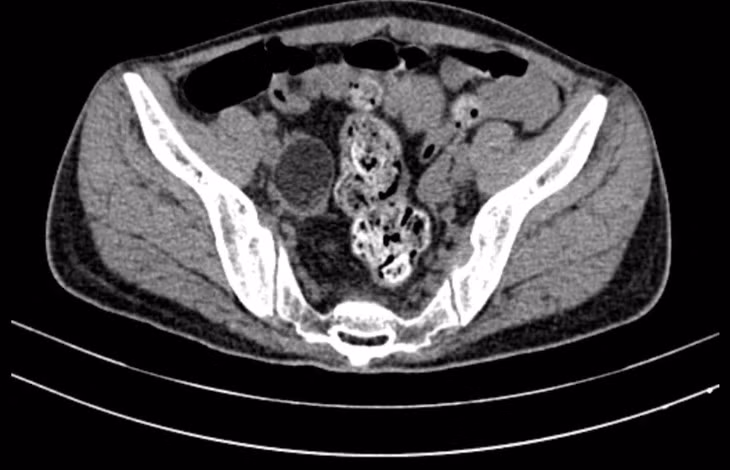

Bác sĩ tiếp tục chỉ định cho bệnh nhân làm lại loạt xét nghiệm nhưng không phát hiện nghi ngờ. Tuy nhiên, hình ảnh chụp MRI sọ não lại ghi nhận tổn thương cũ vùng thái dương trái và tổn thương thùy thái dương hai bên lan rộng hơn so với phim MRI sọ não chụp trước đó một tháng.